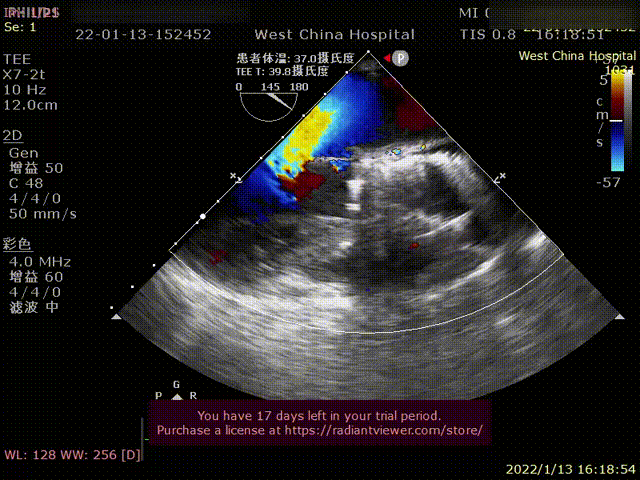

Case 2

患者为69岁男性,因“活动后胸闷,气紧十年余,加重1月”主诉入院。术前超声提示:左心明显增大,LVDD 82mm,LVEF 26%,主动脉瓣重度狭窄伴重度反流。术后即刻主动脉瓣大量反流消失,超声显示LVDD 65mm,左心较术前显著缩小。

术前超声影像